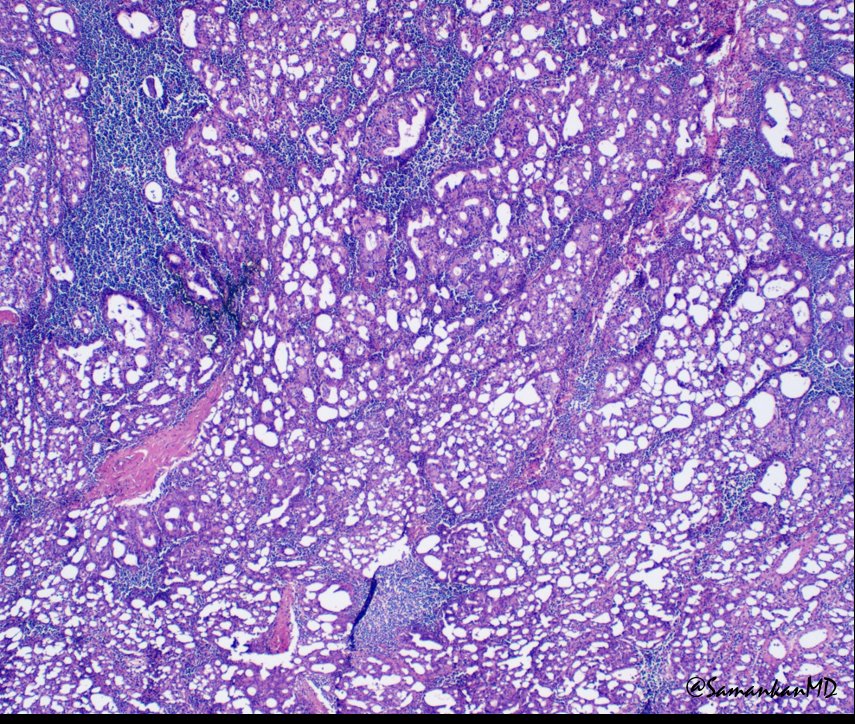

Hot off the press!! Check out this paper by Dr. Brandwein and team: Tall cell variant papillary thyroid carcinoma impacts disease-free survival at the 10 % cut-point on multivariate a… pubmed.ncbi.nlm.nih.gov/35834884/ #HeadAndNeckPath #ENTPath #ThyroidPath